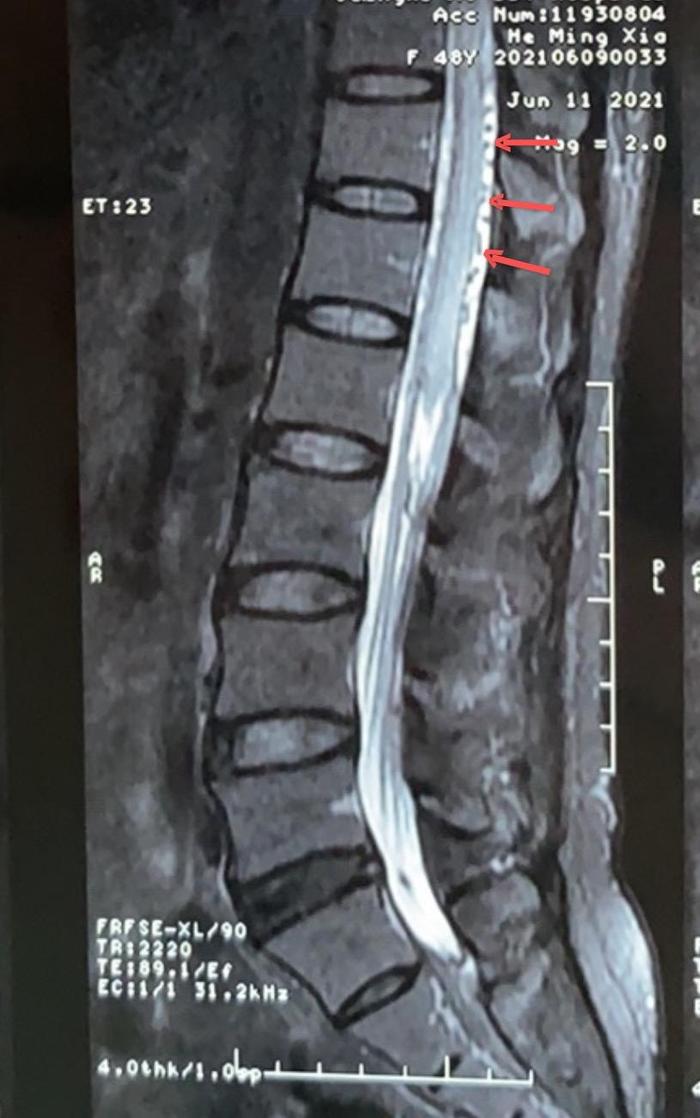

患者女,48岁,广西人,定居海南,自觉双下肢发力发软、麻木、无力,伴有小便困难,大便便秘一年余。在当地大型三甲医院检查胸腰椎MR提示脊髓背侧增粗迂曲血管影,脊髓水肿,高度提示脊髓血管畸形可能。在某医科大学第一附属医院行脊髓血管DSA造影阴性,没有发现异常。症状逐渐加重,来到我院门诊已经坐上轮椅了,患者痛苦不堪。

为积极挽救患者脊髓神经功能,戴大伟副主任医师团队第一时间收治患者入院,行全脊髓血管DSA造影明确左侧髂内动脉分支动脉供血的S1-2骶管硬脊膜动静脉瘘(SDAVF)